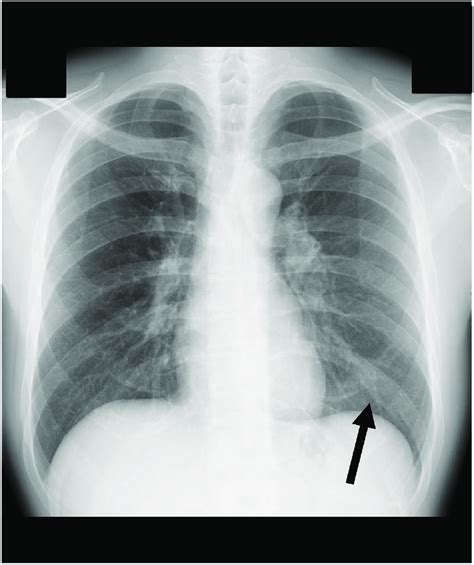

Here are five ways to interpret a normal chest X-ray: * Lung Fields: The lung fields should be clear and free of any abnormalities, such as nodules, masses, or infiltrates. The lungs should also be of equal size and shape. * Heart Size and Shape: The heart should be of normal size and shape, with no signs of enlargement or abnormality. The cardiothoracic ratio, which is the ratio of the heart size to the chest size, should be within normal limits. * Chest Wall and Ribs: The chest wall and ribs should appear normal, with no signs of fractures, deformities, or other injuries. * Diaphragm and Mediastinum: The diaphragm and mediastinum should appear normal, with no signs of abnormalities, such as masses or infiltrates. * Pleura and Airways: The pleura and airways should appear normal, with no signs of abnormalities, such as pleural effusions or airway diseases.

A normal chest X-ray can reveal a lot about a person’s health, including: * Lung Health: A normal chest X-ray can indicate that the lungs are healthy and free of diseases, such as pneumonia or lung cancer. * Heart Health: A normal chest X-ray can indicate that the heart is healthy and of normal size and shape, which can rule out conditions such as heart failure or cardiomegaly. * Chest Wall and Rib Health: A normal chest X-ray can indicate that the chest wall and ribs are healthy and free of injuries or deformities. * Diaphragm and Mediastinum Health: A normal chest X-ray can indicate that the diaphragm and mediastinum are healthy and free of abnormalities.